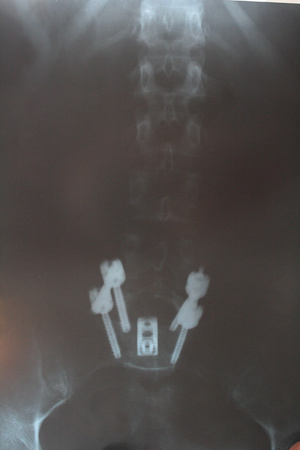

А что у вас с поясничным отделом?Сейчас так, как на фото.

А изначально был спондилолистез истмический нестабильный. Зафиксировали.

Плюс - спондилоартроз, протрузии, как у многих в моем возрасте.